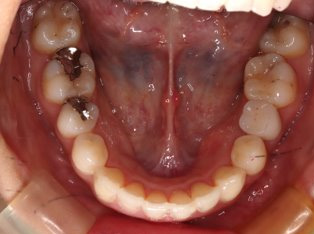

乱ぐい歯、でこぼこがとても酷い状態になります。歯が前後的に重なってしまっている、八重歯になっているなどがこのジャンルに入ります。

顎の大きさと歯の大きさのギャップが大きく、時には歯を抜かないと矯正治療ができない場合もあります。当院では治療期間が長くなるが抜かない治療方針など、一つの治療プランだけでなく、さまざまな可能性の治療方針を説明させて頂くよう心掛けております。こういった考え方はインフォームド・チョイスと言われ近年大切にされている考え方と言われております。

治療前

治療終了前